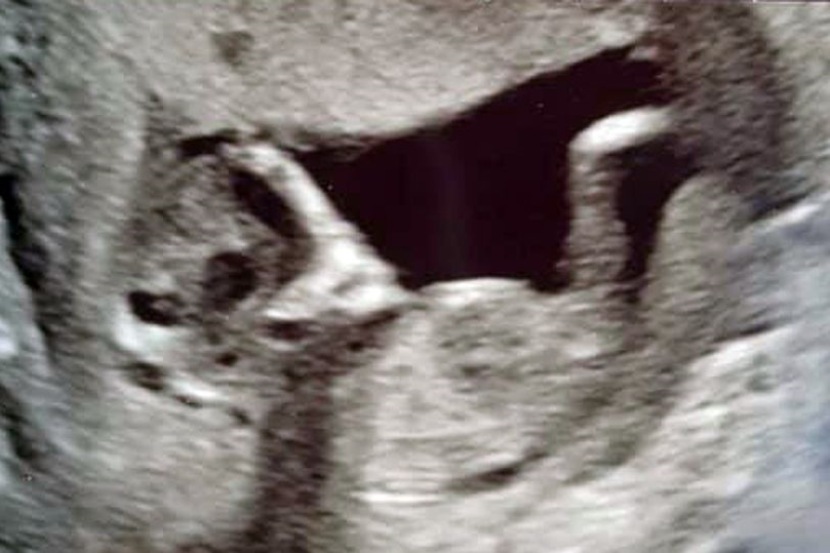

SEORANG gadis terkejut apabila mendapati imej imbasan kehamilan di dalam kandungannya kelihatan seperti 'alien'.

Sophie Scott yang teruja hamil bayi perempuan bertukar panik apabila pasangannya, Stephen Roberts memberitahu imbasan menunjukkan terdapat imej seperti makhluk asing di sebalik kandungan tersebut.

Sophie yang merupakan seorang pelajar dari South Shields, Tyneside di United Kingdom berkata: "Kami dapat melihat mata tambahan di sebalik bayi itu, dan kepalanya berbentuk seperti alien."

Pemeriksaan empat minggu kemudian bagaimanapun mendapati kandungan berusia 16 minggu itu hanya mempunyai seorang bayi. - Mirror UK